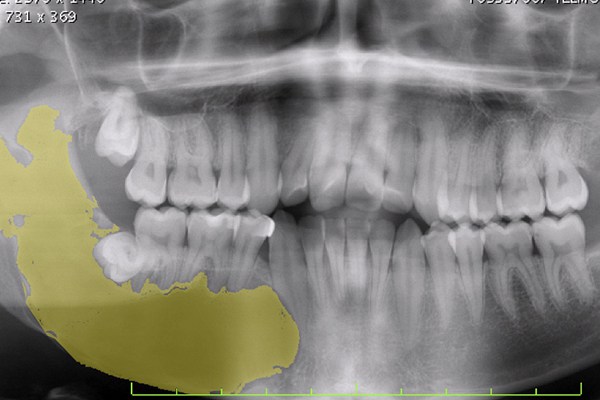

Os atos cirúrgicos mais recorrentes nesta área consistem em extrações de dentes com cáries muito extensas e não restauráveis, dentes inclusos ou semi-inclusos.

- excisão de quistos;